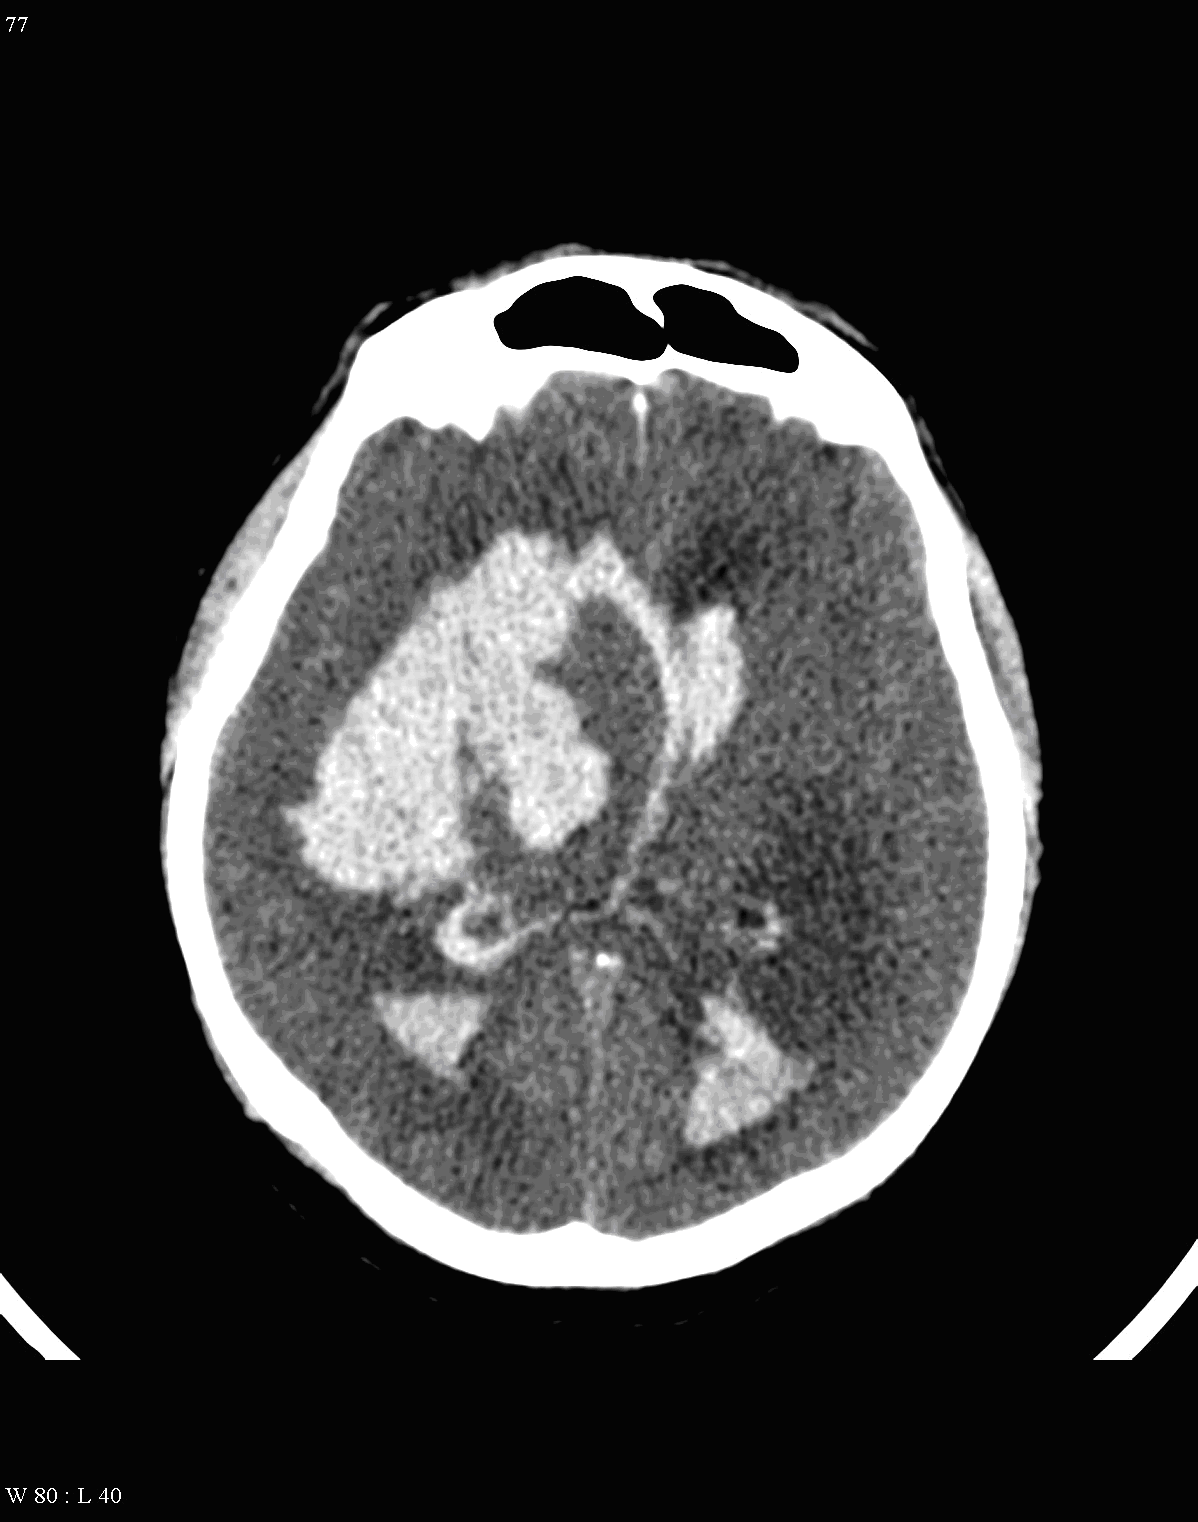

On CT images acute bleeding always presents as hyperdensity. (One has to keep it mind that hyperdensity of the blood is affected by the hematocrit levels, hence making the diagnosis more difficult.) Intraparenchymal blood is dominated by a destructive appearance (mass-effect) and it is surrounded by hypodensity as a sign of perifocal edema. It often breaks into the ventricles. In patients lying in a supine position they collect (sediment) at the occipital horn of the lateral ventricles, creating a hyperdense liquid-to-liquid levels. Later on, the density of blood decreases and shows a peripheral ring or rim-like contrast enhancement without mass-effect.

CT angiography examination is usually advisory in order to confirm the site of the bleeding. It is also effective when a hemorrhagic tumor is in the differentials, although complete differentiation might only be achieved by follow-up examinations. CTA is also essential in the diagnostics of multiple aneurysms (which are prevalent in 20-30% of the cases based on autopsy reports.) In case of a subarachnoid hemorrhage the consequently developing hydrocephalus and its degree might only be detected on follow-up CT examinations. It is very important to note that an initial brain aneurysm rupture might be followed by a second one within the first 7 – 10 days and the resulting vasospasm carries a much higher risk of mortality than the one at the time of the first SAH. This is why the scrutonius review of the acute diagnostic imaging is essential and it plays a fundamental role in patient treatment. Open brain surgery of the aneurysm (clipping) has been replaced by catheter angiography (DSA) nowadays. The aneurysm is either filled up with thrombogenic coils through its neck or recently bypassing stents are inserted to exclude the aneurysm from the cerebral circulation.

CT can usually lead to definitive diagnosis regarding brain tumors. A non-territorial localization (as opposed to arterial occlusion) of a usually “glove” shaped perifocal hypodense zone is highly suspicious for a tumor.

MRI has the greatest sensitivity in the detection of neoplastic brain lesions. The relaxation time of tumor is usually longer than that of the surrounding normal tissues. Therefore on T1W images neoplasms have slightly weaker signal intensity, while on T2W images they are more hyperintense than normal parenchyma. This signal pattern can be very characteristic and has great diagnostic value. However, secondary neoplastic signs, such as mass-effect of the tumor cannot be neglect either. A space occupying lesion can cause:

- the dislocation of the midline structures,

- the impression or dislocation of the ventricle,

- hydrocephalus as a sign of liquor obstruction

Tumors frequently presenting with hemorrhage are: choriocarcinoma, melanoma, metastases of renal cell carcinoma and bronchial carcinoma, pituitary adenoma, glioblastoma multiforme and medulloblastoma.